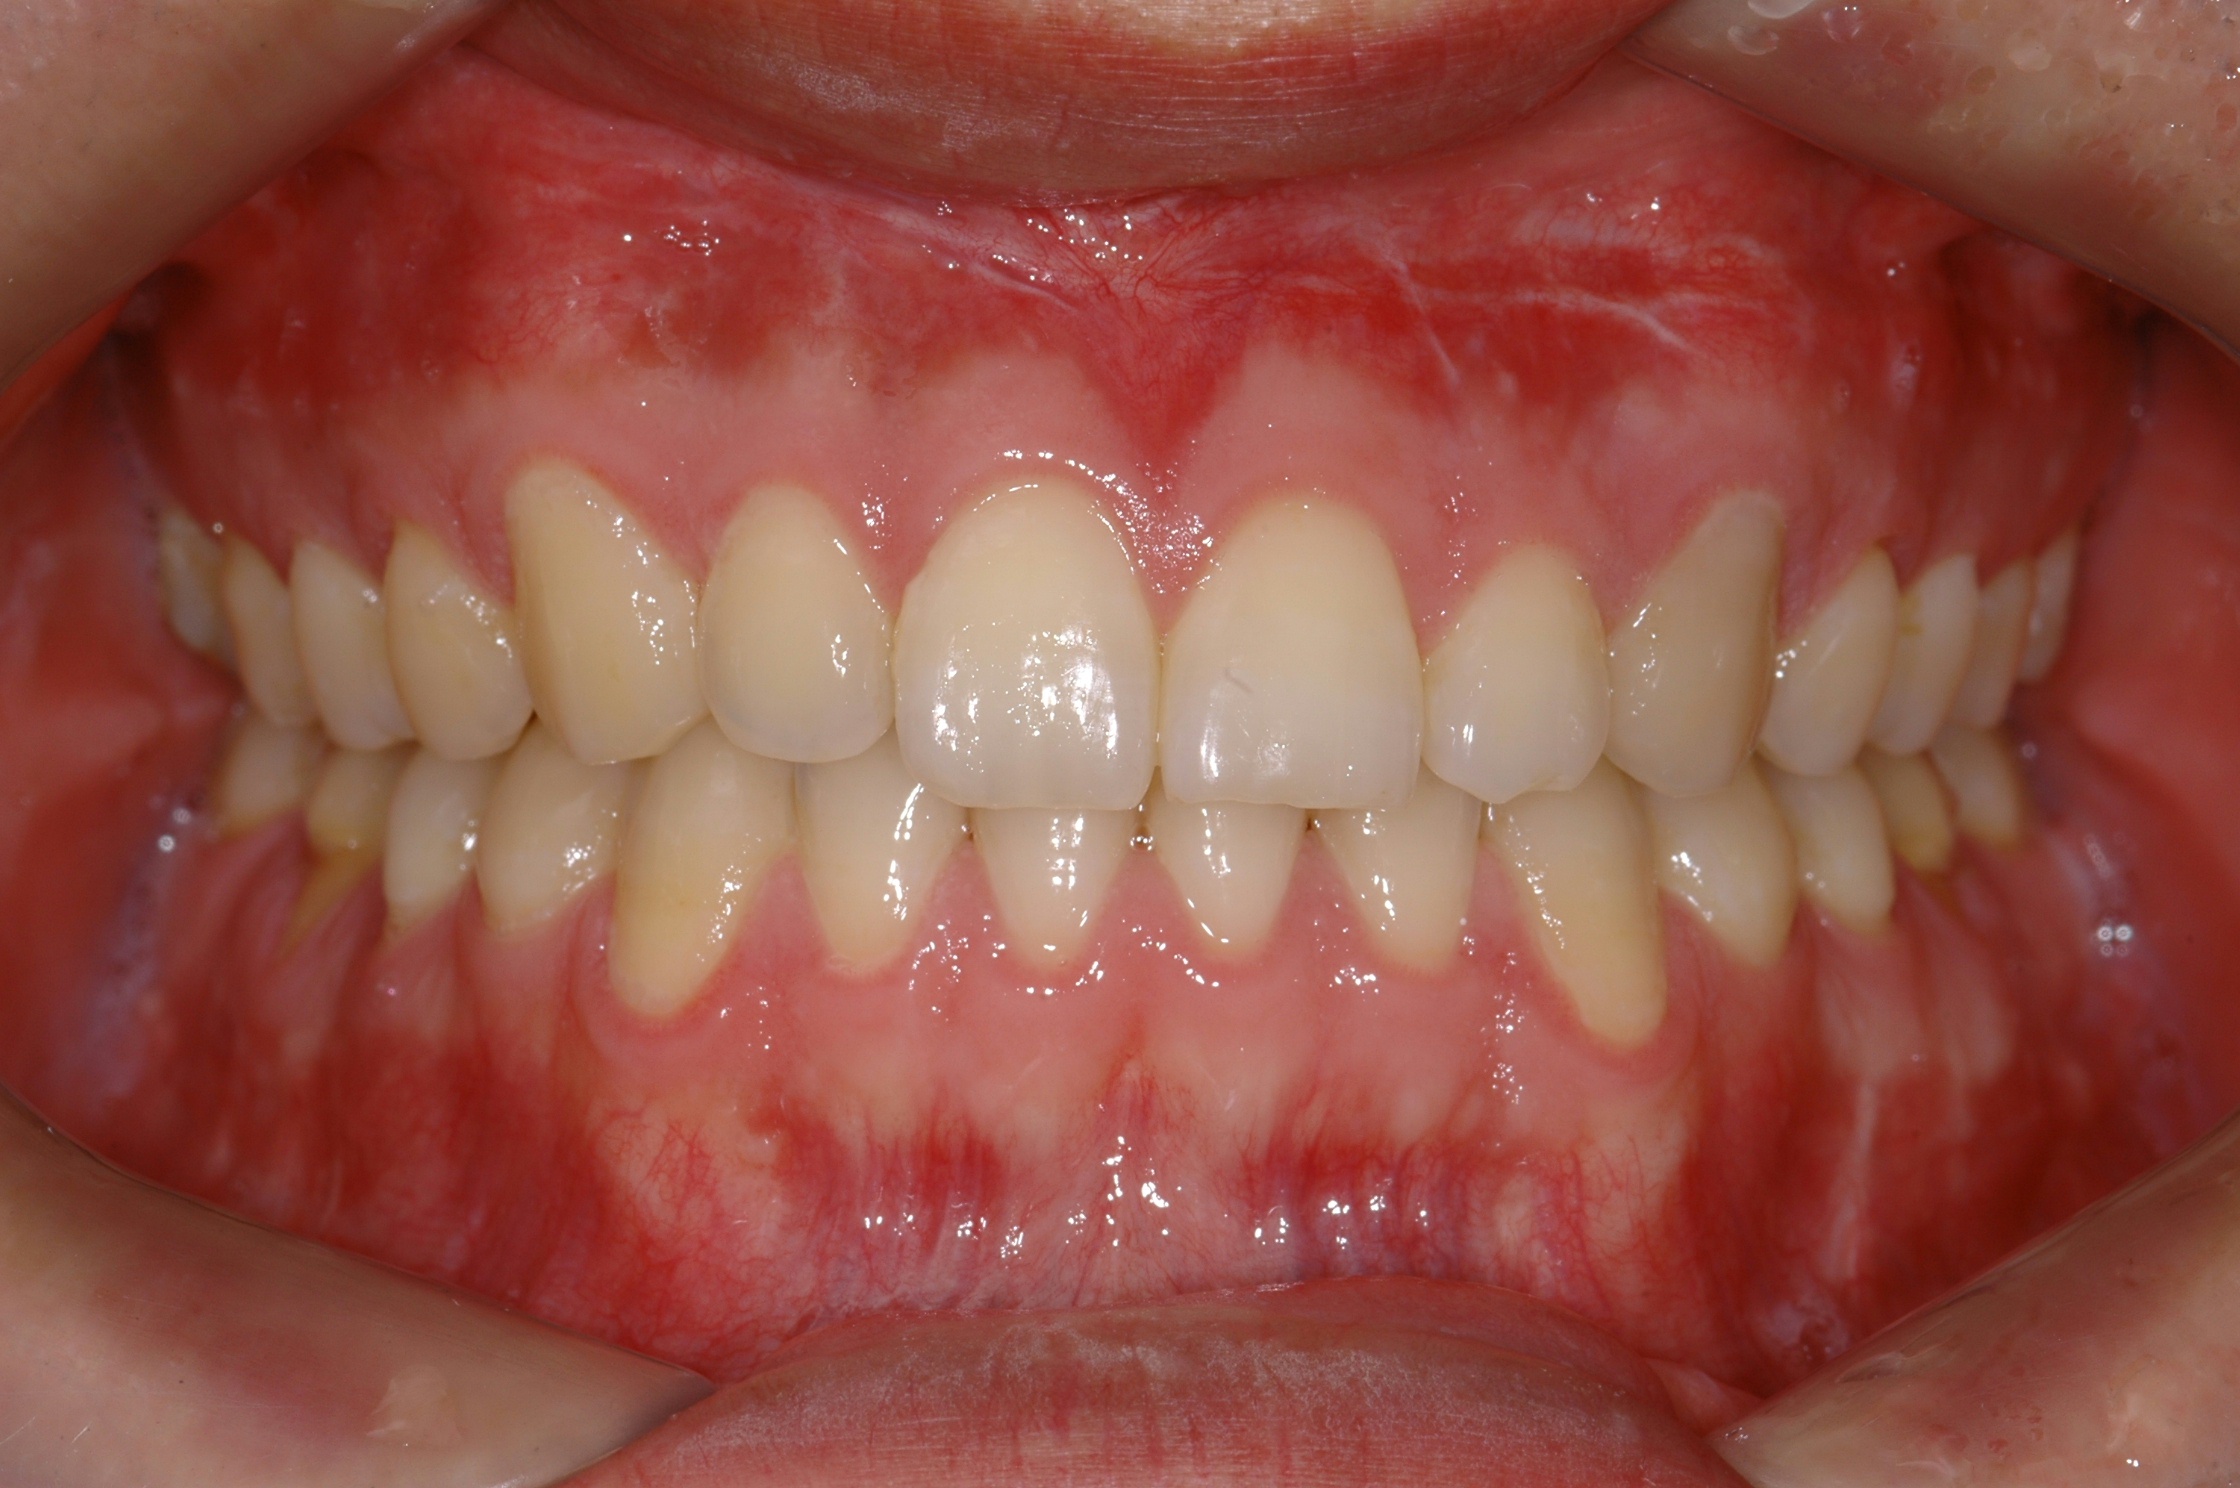

치료 후 사진입니다.